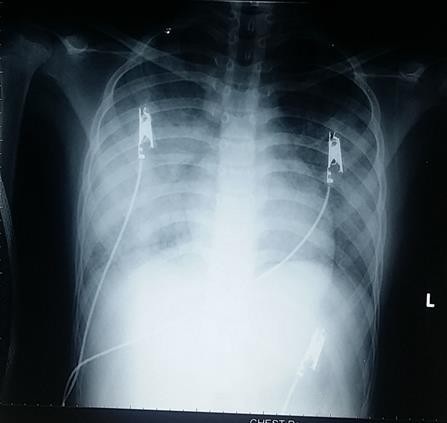

Qua xét nghiệm, X-Quang, kiểm tra chuyên sâu, sinh thiết nội soi lồng ngực, đồng thời hội chẩn với các chuyên gia trong và ngoài nước…, các bác sĩ chẩn đoán bệnh nhi mắc bệnh lắng đọng Hemosiderin tại phổi.

Theo Ths.BS Nguyễn Thị Hồng Huyên (Khoa Hô hấp 1), qua các lần theo dõi, bé không còn biểu hiện thiếu máu, không ho ra máu và XQ tổn thương phổi cải thiện. Tuy nhiên, cũng cần theo dõi và đánh giá thêm trong khoảng thời gian tiếp theo.